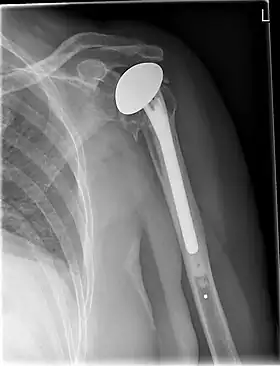

![]() X-ray of a shoulder prosthesis | |

Shoulder replacement is a surgical procedure in which all or part of the glenohumeral joint is replaced by a prosthetic implant. Such joint replacement surgery generally is conducted to relieve arthritis pain or fix severe physical joint damage.[1]

Various materials can be used to make prostheses, however the majority consist of a metal ball that rotates within a polyethylene (plastic) socket. The metal ball takes the place of the patient's humeral head and is anchored via a stem, which is inserted down the shaft of the humerus. The plastic socket is placed over the patient's glenoid and is typically secured to the surrounding bone via cement.[13]